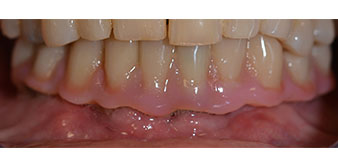

Una vez transcurrido el tiempo necesario para la integración ósea, puede llevarse a cabo la impresión definitiva del implante para realizar la prótesis definitiva de manera acorde (figs. 19 y 20). En este paso, el responsable del tratamiento y el paciente pueden decidir conjuntamente si es preferible un revestimiento cerámico o plástico y una estructura de zircón o de metal. En este caso, dado que el pronóstico de la dentición del maxilar superior era poco claro y la pieza dental 24 estaba elongada, el equipo del Dr. Pascu se decidió por un revestimiento de plástico, ya que, por lo general, es mucho más fácil de ajustar y puede adaptarse a la nueva situación del maxilar superior.

integración ósea

Fig. 19

Implantes

Fig. 20